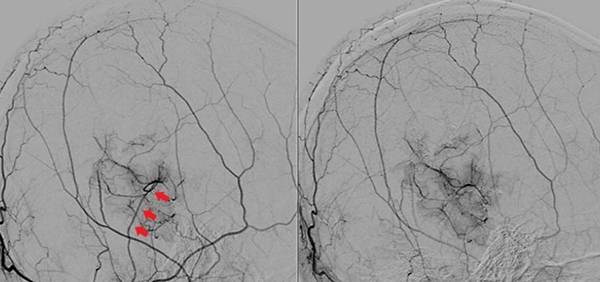

Caso clínico #1: PR masculino de 20 años sin antecedentes clínicos, estudiado por cefaleas de varios meses de evolución. La RMN no presenta lesiones y la ARM evidencia una disminución del flujo de la arteria cerebral media derecha. La ADC muestra la estenosis progresiva de la arteria carótida interna derecha supraclinoidea, ausencia de opacificación del origen de la arteria cerebral media y anterior, presencia de vasos de MM con escasa circulación colateral desde carótida interna izquierda a través de la comunicante anterior; corresponde a un grado 3 de Suzuki (Fig. 1). Se realizó una revascularización cerebral combinada: un bpTS más EDMS derecho, la evolución postoperatoria fue sin complicaciones y la ADC diferida muestra una buena perfusión cerebral a través del bypass y la sinangiosis (Fig. 2). El control clínico a 4 años es favorable y las imágenes de RMN y RMA evidencian ausencia de nuevas lesiones isquémicas y adecuada revascularización.

Fig. 2 Caso clínico #1. ADC postoperatoria en frente (izquierda) y perfil ampliado (derecha), bp TS derecho con un buen calibre en la arteria temporal superficial (aTS) y muy buena perfusión cerebral